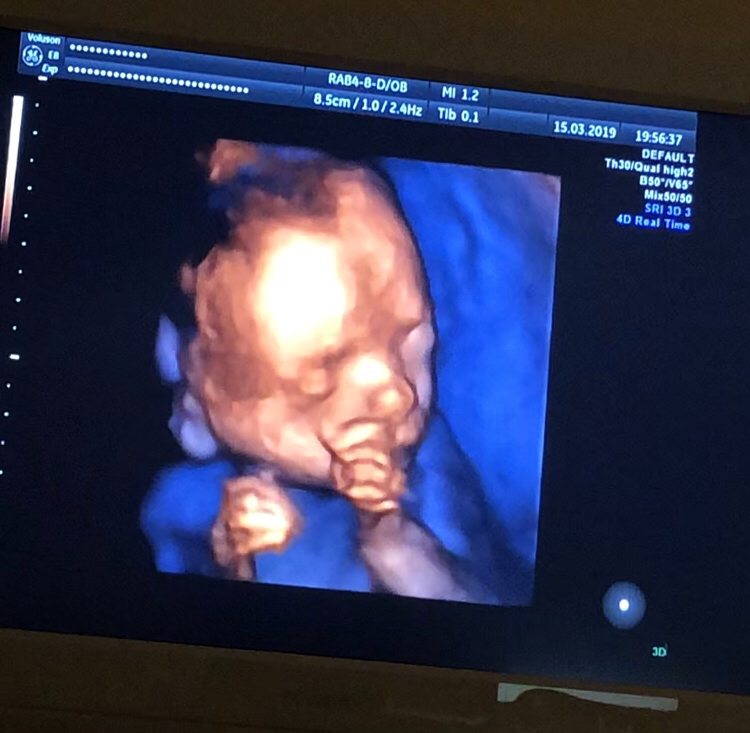

20 недель,2-ой скрининг,фото 3D

Результаты: УЗИ, КТГ, доплера, скринингаВчера было ровно 20 недель,2 скрининг,посмотрела как он вырос,такой хорошенький,палец сосал)) весит 350 гр. Все у него хорошо ттт. Хоть тут многие и говорили,что в 13 недель это рано для определения пола,но я считаю что нет,все зависит от врача,вчера специально даже спросила ее ошибалась ли она на сроке 13 недель с полом(первого,второго и этого третьего езжу только к ней скрининги делать), сказала,что с 13 недель она ни разу не ошибалась,что с такого срока уже все понятно. Вчера только подтвердила,что это ещё один мальчик😂. В спб она одна из лучших узи специалистов и кто скрининги делает идеально. Вдруг кому понадобится фамилия ее Лисина,работает в роддоме на фурштатской. Малыш вчера идеально лежал,шевелился во всю,показывая себя во всей красе и во всех ракурсах,видимо хотел угодить отцу,который тоже приехал посмотреть)) И фото мне на память,на ББ всегда проще зайти и посмотреть фото,чем потом искать их дома)) 😄😄